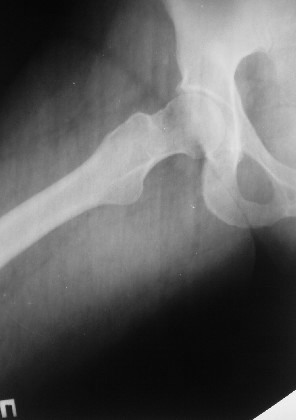

Уважаемые коллеги! Хотел-бы обсудить интерессный, на мой взгляд, случай.На консультацию пришла женщина 45 лет с отводящей контрактурой правого бедра.

Из анамнеза: в ноябре 2002г. оступилась,упалана трап самолета (на верхней площадке, сразу при выходе из салона) на правый тазобедренный сустав, а затем - вниз на землю на ноги и ягодицы. Потеряла сознание от боли. Доставлена в больницу по месту жительства, лечилась консервативно с диагнозом кокцигодиния.На рентгенограмме от 27.11.02г. вывиха копчика не определяется (снимок идентичен представленной R-грамме от28.11.03г., кроме этого есть нормальная R-грамма копчика в боковой проекции).Через три недели стала ходить, но привести правую ногу в тазобедренном суставе не могла. Сейчас ходит отведя кнаружи правое бедро и голень, как ножку циркуля (фото 1). Неврологических нарушений нет. По просьбе врачаможет на 30-40 секунд поставить ноги вместе (фото 2). При этом испытывает сильную тянущую боль и ощущение "вывернутости" в правом тазобедренном суставе. Эти ощущения заставляют вновь отвести бедро. В положении лежа разогнуть бедро полностью не может из-за болей в ягодичной мышце (фото 3). Сгибание также ограничено из-за болей (фото 4). Отведение в положении лежа возможно в том же объеме, что и стоя (фото 5). Заподозрен старый разрыв правого крестцово-подвздошного сочленения.Выполнено R-исследование и КТ(в приложении). По-поводу деформации лонного сочленения выяснен гинекологический анамнез. Роды одни, нормальные в 22 года. Из роддома выписана на 8 сутки, нарушения походки не было, R-графия таза не проводилась. Вопросы на обсуждение: 1. Диагноз либо алгоритм дальнейшего обследования. 2. Лечебная тактика (в первую очередь возможность и целесообразность оперативного лечения).

Уважаемый Юрий Алексеевич, сделаны ли пациентке более дистальные срезы КТ с захватом области тазобедренного сустава? Учитывая давность травмы, могли присоединиться и дистрофические процессы в субхондральной кости головки и впадины. Изменения в капсуле будут хорошо видны на УЗИ, особенно в сравнении со здоровой стороной. Эффективность лечебно-диагностического введения гормональных препаратов, на мой взгляд, сомнительна ввиду давности патологического состояния. При такой стойкой и давней контрактуре без операции вряд ли можно обойтись. Под наркозом амплитуда на разгибание должна увеличиться, усилить эффект можно тено-миотомиями заинтересованных групп мышц, капсулотомией + в послеоперационном периоде хорошее консервативное противовоспатлительное лечение с укладками на разгибание.Что мешает приведению пока не ясно, во встретившихся в нашей работе аналогичных ситуациях причиной был формирующийся медиальный остеофит головки, выталкивающий её из впадины.

эластичности этих мышц. В положении приведения происходит их перерастяжение, создается болевой синдром. На представленных снимках, к сожалению, эти структуры не определяются.